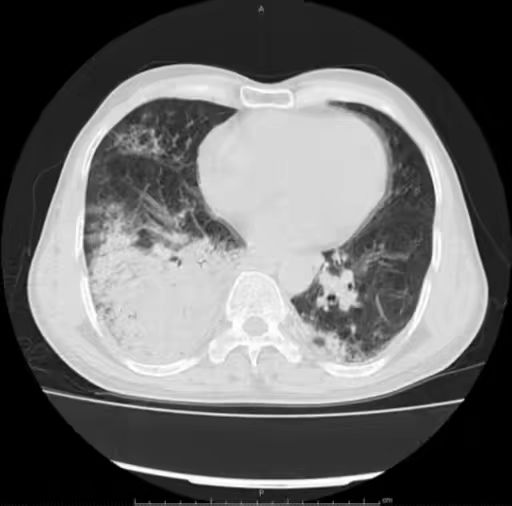

男,66 岁,发热伴寒颤、咳嗽咳痰 2 天。WBC 1.56×10^9/L,中性粒细胞 1.37×10^9/L,淋巴细胞 0.13×10^9/L,单核细胞 0.05×10^9/L,嗜酸细胞 0,CRP 183.1 mg/L,PCT 58.07 ng/mL,B 型尿钠肽前体 2340 ng/L。

胸部 CT 如下:

肺炎链球菌肺炎多为肺泡性肺炎,少数血播肺炎链球菌肺炎好发于老年人及免疫力低下人群,PCT 明显增高。影像上,早期在血管炎的基础上仍能见到按肺小叶充填及闲置的表现(肺泡性肺炎的表现),而大片实变影已不能分辨是否为血管炎(病灶边缘磨玻璃仍可看出血管炎),在肺尖段不会占据整个层面(与铜绿假单胞菌肺炎不同),而在下肺往往表现为齐头并进的特点,分布上多上肺优势。